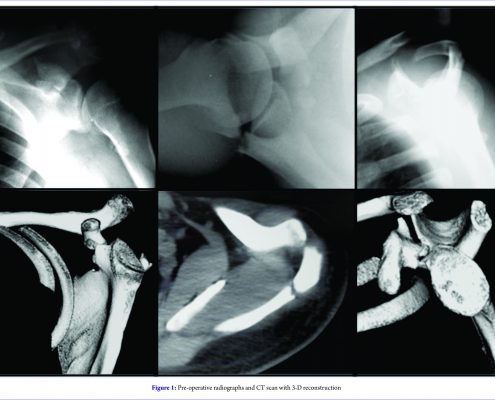

A Comprehensive Review of Triple Disruptions of the Superior Shoulder Suspensory Complex and Case Report